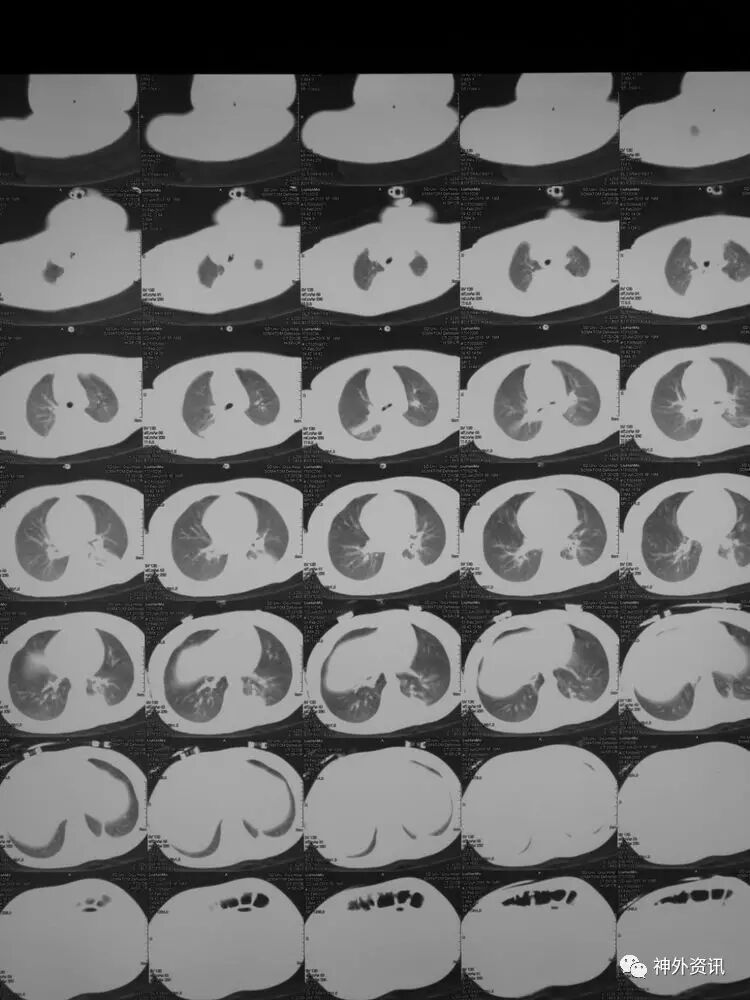

2017.2.8:术后9天,复查颅脑及胸部CT,结果显示双侧脑沟脑回及环池显示清晰。颅压控制,拔除引流管探头,头部敷料稍加压包扎,此时已更替力月西为丙泊酚,停用呼吸机。

胸部CT及超声显示双肺底存在肺不张: